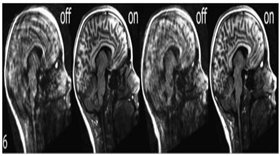

| 뇌구조 MRI 영상 | TI | 254명 | 1인당 362개 정보 |

| 뇌기능 MRI 영상 | EPI | 254명 | 1인당 7000장 이상 |

| 뇌영상 | ![]() |

데이터 포맷 속성 명 참조 |